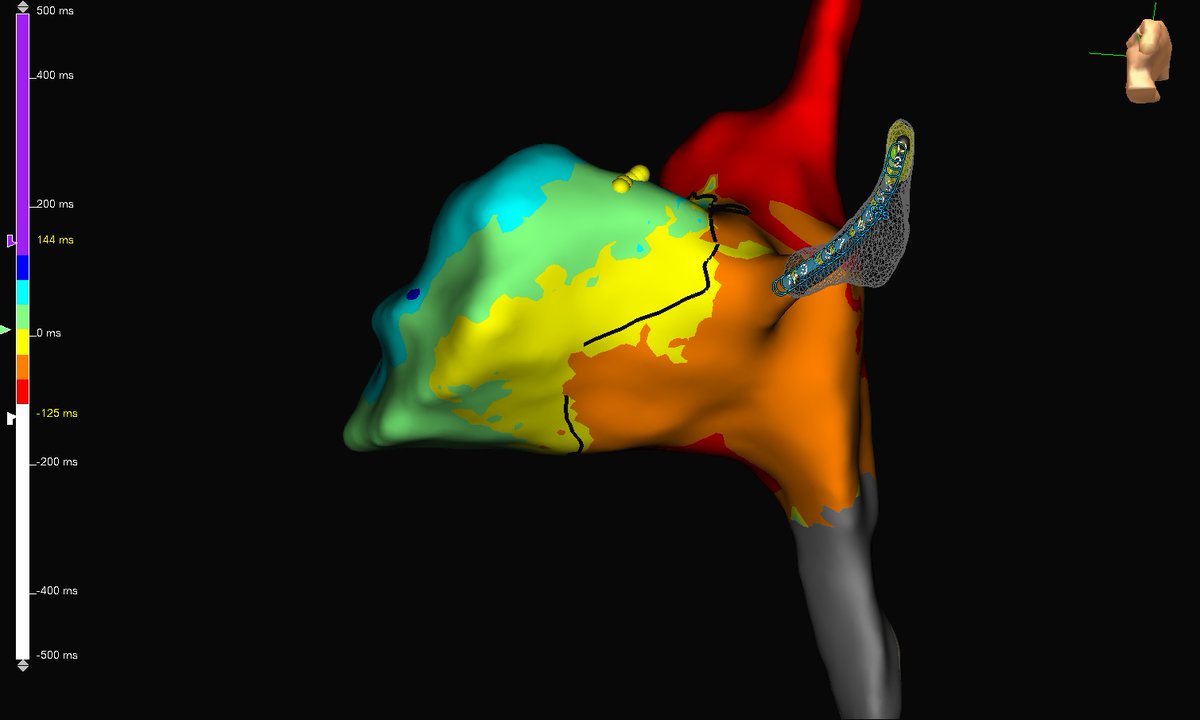

Friday flutter with this beauty of an RA circuit. #HDgrid was used to map this circuit and termination occurred within 1 sec of RF. #mapmoreburnless @AbbottCardio

subparsonsmaps's tweet image. Friday flutter with this beauty of an RA circuit. #HDgrid was used to map this circuit and termination occurred within 1 sec of RF. #mapmoreburnless @AbbottCardio